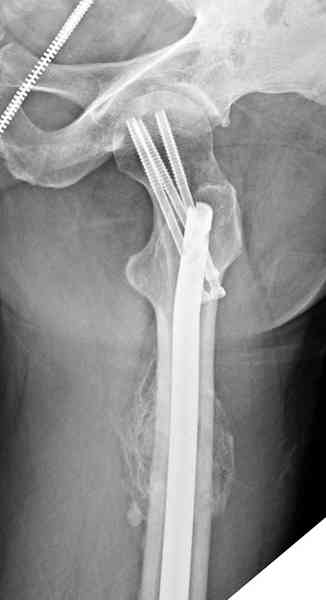

На второй день (7) обнаружен пропущенный перелом,

сделаны Компьютерная Томограмма

и проведены шурурпы через и спереди штифта без удаления.

Послеоперационные снимки